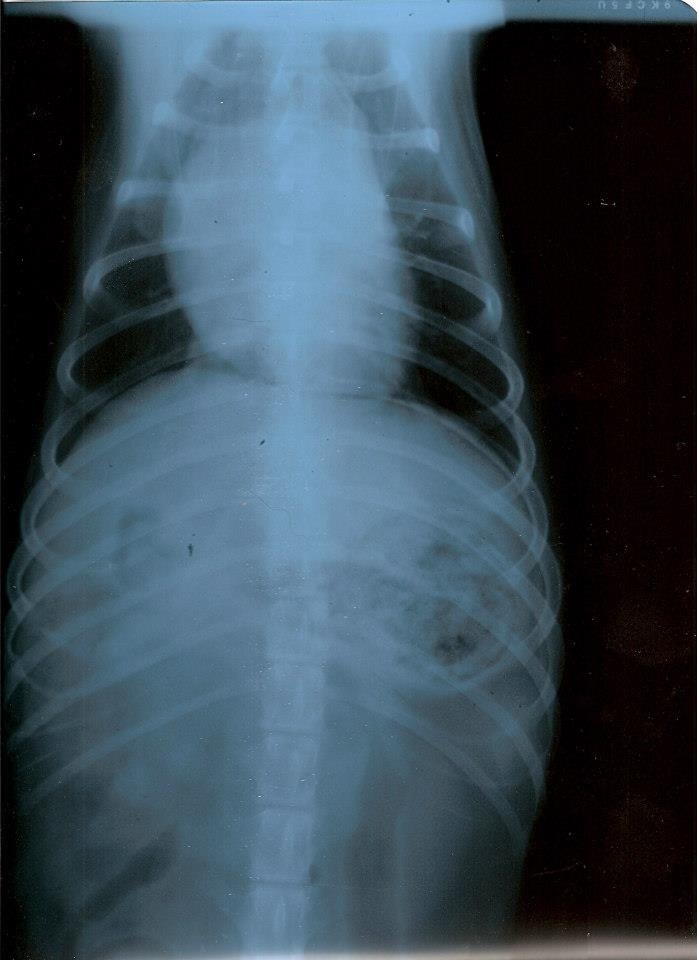

Ciao Mandy: dagli rx posso dirti al 99% che non è tumore...non li vedo...ed hai fatto stra bene a mandarmi le due proiezioni.

A questo punto però dovrei farti io alcune domande: 1) Difficoltà a respirare hai detto: fa fatica ad inspirare o ad espirare? 2) tossisce? 3) Hanno rilevato soffi cardiaci? Io, visto che dici essere peggiorato negli ultimi mesi, inserirei nella terapia (non vorrei però passare sopra i medici che lo stanno curando, quindi il mio è un consiglio nel massimo rispetto di colore sono li col cane, non potendolo io vedere) un diuretico. Il quadro polmonare mi sembra ascrivibile ad un edema polmonare. Quindi in tal caso darei Lasix o Diuren alla dose di 2 cpr ogni 12 ore. Questo lo darei anche senza avere le 3 risposte alle domande di cui sopra. Il profilo cardiaco mi sembra aumentato di dimensione..... Fammi sapere!!! I morti li portano via freddi.

Ho letto ora i tuoi commenti alle foto.....ero concentrato sulle radiografie.

Bene allora.....ma se ripeggiora, il diuretico lo darei lo stesso. Se l'animale mangia non ha effetti collaterali.... I morti li portano via freddi.

Non ti è arrivata la mail? Infatti mi sembrava strano che non mi avessi risposto. Te la incollo qui. 1. Entrambi 2. No 3. No Martedì sera gli hanno fatto una puntura di analgesico e una di un anti infiammatorio e con quelle è passato il peggio. Sembrava che stesse annegando. Siccome nella lastra si intravede un pezzo di osso nello stomaco pensano adesso che avesse avuto un gran dolore allo stomaco e respirava male per quello. Adesso sta bene il piccolo highlander. Aggiungo il diuren? |